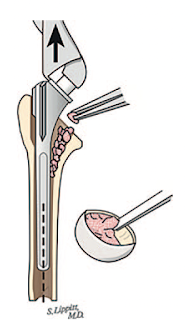

Bone is not removed from the canal by reaming

instead, a stem diameter is selected that is smaller than the internal diameter of the diaphysis, yielding a small filling ratio without violating the bone of the canal.

The irregular internal anatomy of the humerus

is fit to the stem using impaction grafting

The security of this fixation obviates the need for ingrowth surfaces on the implant, which can complicate removal of the stem should it become necessary.

The bone graft spreads the load broadly across the interface between the stem and bone minimizing the risk of stress shielding.